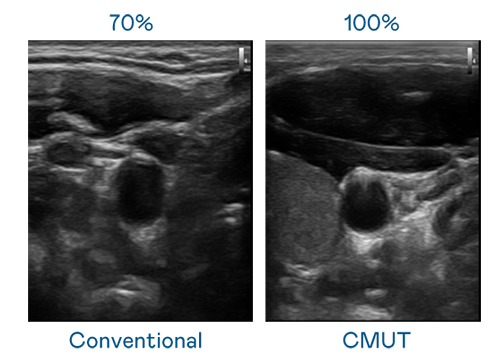

CMUT 技术是一种用电容式微机电元件来产生超音波讯号的技术。与传统 PZT 压电式技术相比,CMUT 频宽增加 30%,更宽频的超音波讯号让影像解析度大幅提升,是实现高影像品质医疗超音波扫描、促进精准医疗发展的关键技术。

大频宽带来超清晰影像

超音波影像的解析度高低,首先取决于探头能发出的讯号频宽。17c官网在线免费观看 CMUT 可提供高清晰的超音波讯号,提供高频宽、高灵敏度、影像纹理细节更高的超音波影像,协助医护人员缩短影像判读时间及利用精准的医疗影像进行诊断。